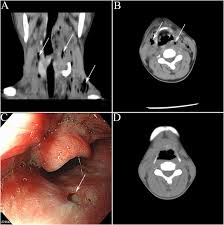

Early Diagnosis Of Necrotizing Fasciitis Goh 2014 Bjs British Journal Of Surgery Wiley Online Library

Early Diagnosis Of Necrotizing Fasciitis Goh 2014 Bjs British Journal Of Surgery Wiley Online Library from bjssjournals.onlinelibrary.wiley.com